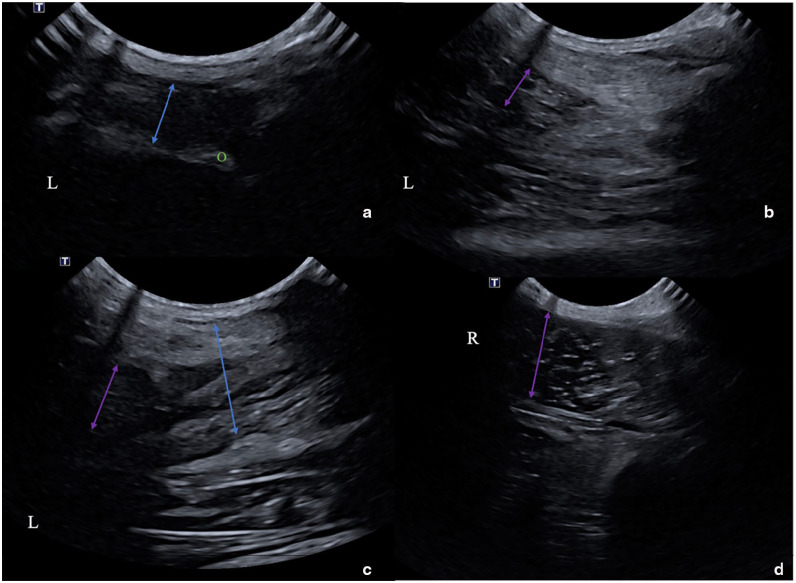

Case summary: Major avulsion of the triceps tendon insertion was diagnosed in a 7-year-old domestic shorthair cat 3 weeks after developing sudden severe weightbearing lameness of the left thoracic limb. Diagnosis was confirmed with orthopaedic, radiographic and ultrasonographic examinations. The absence of adequate bone stock prevented the use of conventional techniques for tendon reinsertion. Instead, the tendon was reattached using an ultra-high molecular weight polyethylene (UHMWPE) ExtraTape prosthesis. It was stitched into the triceps tendon and superficial fascia, then passed through a bone tunnel drilled in the olecranon and secured with a preassembled cortical button. No external coaptation was used. Although the cat experienced temporary mild lameness, pain-free and satisfactory use of the left thoracic limb was observed 4 weeks postoperatively. By 12 weeks, the cat's gait had returned to normal, with no gap between the tendon and the olecranon. The cat resumed normal gait and range of motion 8 months postoperatively.